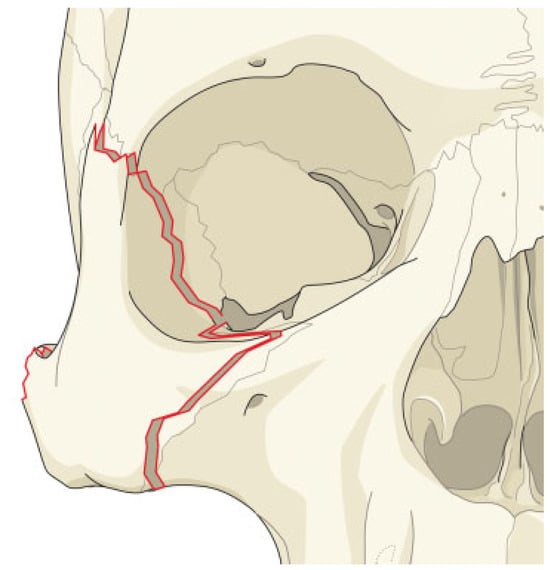

The authors defined simple LOWF as any fracture consisting of two boney pieces (Figure 1) and comminuted fractures as any fracture consisting of three or more pieces (Figure 2). Only patients who sustained fractures through primary trauma were included in this study. This excluded patients whose fractures were due to tumor resection or patients with a history of previous fractures of the lateral orbit. The senior investigator (W.S.) of this study identified the presence of all fractures, which were also confirmed upon review of the official radiology report.

Figure 1.

Simple lateral orbital wall fracture.